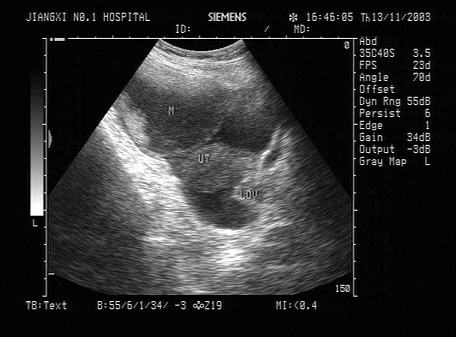

某患者左肾超声声像图如下,最可能的诊断为()。

A:多发性肾囊肿

B:肾结核

C:多囊肾

D:重度肾积水

E:中度肾积水